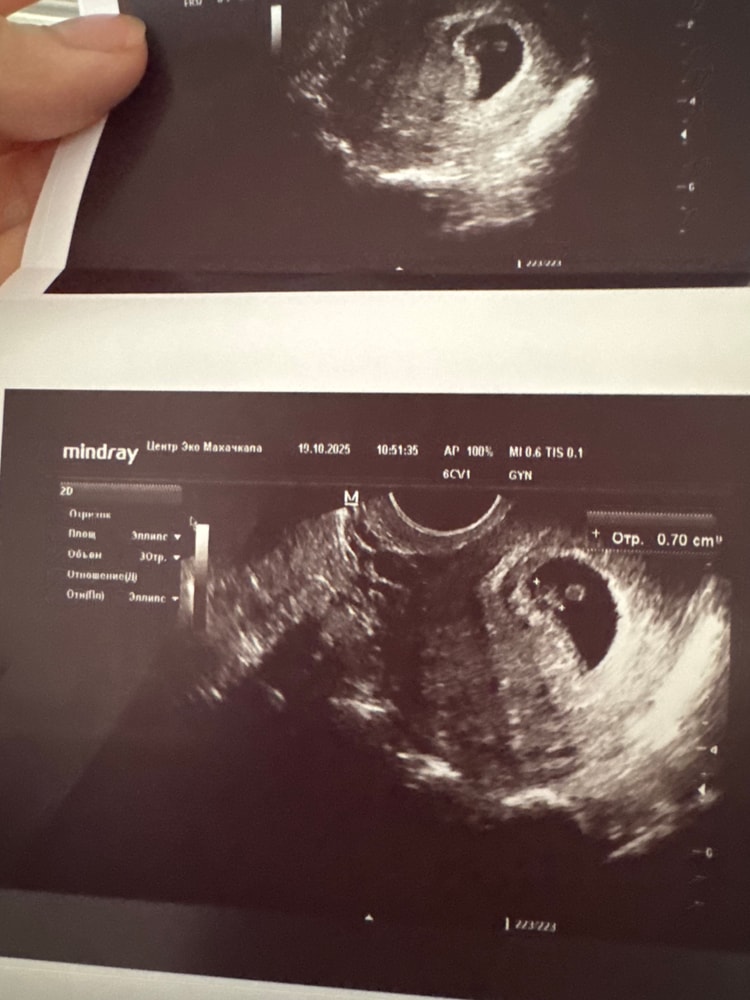

А что в описании? Странная форма. Ещё похоже на отслойку сбоку. Возможно такой ракурс.

Джеллибин, врач сказала отслоек нет и всё в порядке , но меня все равно беспокоит . Говорит, и сердце и ктр и пя в норме

Джеллибин, единственное есть небольшой тонус матки, может из-за этого

Похоже на тонус верхней стенки матки , но такое может быть как только датчик вводят в матку ....